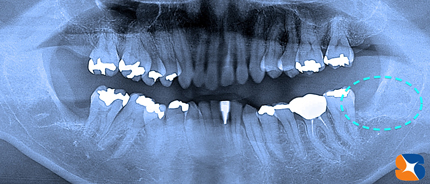

お口全体のレントゲン写真。向かって左が3ヶ月前に抜いた痕。向かって右が今回の依頼場所です。

横向きに生えている親知らずのほんの一部だけが見えています。